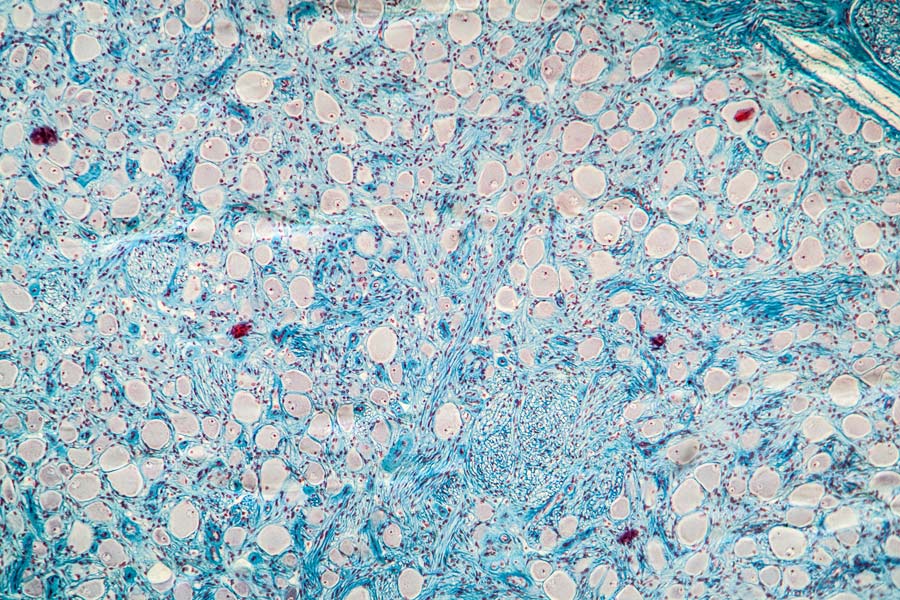

研究人员进行了一项实验,以评估模型模拟的上皮形态发生。成人组织的闭合导致瘢痕的形成。然而,胚胎和幼虫组织有能力以无缝的方式完成愈合过程。幼虫组织果蝇(一种小果蝇)被选中进行调查。的果蝇幼虫翼代成像盘是由一层紧密包装,高柱状细胞组成的上皮。这些细胞似乎布置成层,但它们实际上附着在基底膜上。该组织是用于研究三维伤口愈合细胞行为的理想实验系统。

使用脉冲TiSa激光损伤翼盘上皮,使用3D延时共聚焦显微镜每3分钟记录伤口愈合反应的图像。在模型中创建了一个类似的伤口,通过软化和去除降解的细胞和渐进的伤口闭合来模拟伤口正面和侧面的收缩,以及随后在伤口边缘插入(改变位置)的细胞。

实验测量了五个独立翼盘上的伤口,并取平均值。在伤后的前72分钟,通过手工追踪伤口周围来量化翼盘顶端伤口区域的演变。在伤口愈合过程中,由于顶端肌动球蛋白包线的形成,伤口周围在图像中特别清晰,这是一种能够收缩将伤口边缘向内画出的蛋白质复合物。